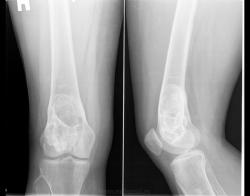

Патологический перелом дистального метафиза бедра, в котором определяется большой участок деструкции многокамерной структуры, занимающий весь поперечник кости, окаймленный ободком склероза, слегка вздувающий кость. Кортикальный слой резко истончен. Остеопороз в проксимальном эпиметафизе б/берцовой кости. Склоняюсь к костной кисте. Через 2 года на месте перелома динамика развития склеротических изменений (тенденция к самоизлечению кисты? хотя не могу исключить замещение ткани кисты трансплантатом, т.е. оперативное вмешат-во), уменьшение выраженности остеопороза в проксим. эпиметафизе б/берцовой кости.

Был патологический перелом? Остеобластокластома? Или фиброзно-кистозная дисплазия?

Представлен случай гиперпаратиреоидной остеодистрофии. А лечение соответственно - удаление аденомы паращитовидной железы. На кости операций не было.